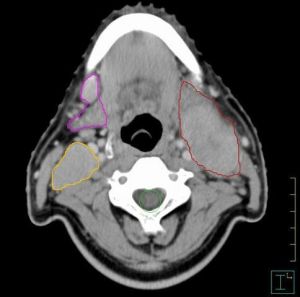

為方便表述淋巴結分布 1991年美國發表了頸淋巴結臨床分區和亞區的劃分(圖2),被各國醫師廣泛套用。

Ⅰ區:包括頦下區及頜下區淋巴結。

ⅠA:頦下區,無臨床重要性。

ⅠB:頜下區,為口腔腫瘤轉移所在。

Ⅱ區:頸內靜脈淋巴結上區,即二腹肌下, 相當於顱底至舌骨水平, 前界為胸骨舌骨肌側緣,後界為胸鎖乳突肌後緣。

ⅡA:頸內靜脈淋巴結, 為頭頸腫瘤主要淋巴引流集中區域,是第1站前哨淋巴結。

ⅡB:位置在後上,被胸鎖乳突肌覆蓋,這部分淋巴結常常是鼻咽癌的轉移處。外科頸清掃術後復發也常在此處。

Ⅲ區:頸內靜脈淋巴結中區。從舌骨水平至肩胛舌骨肌與頸內靜脈交叉處,前後界與Ⅱ區同。

Ⅳ區:頸內靜脈淋巴結下區。從肩胛舌骨肌到鎖骨上,前後界與Ⅱ區同。

Ⅴ區:包括枕後三角區淋巴結(或稱副神經淋巴鏈)及鎖骨上淋巴結。前界為胸鎖乳突肌後緣,後界為斜方肌前緣,下界為鎖骨。

ⅤA:脊副神經淋巴結

ⅤB:鎖骨上淋巴結。

一般臨床處理可以混合ⅤA和ⅤB,但深入討論鎖骨上淋巴結問題,應該分開。

Ⅵ區:內臟周圍淋巴結(或稱前區),包括環甲膜淋巴結、氣管周圍(喉返神經)淋巴結, 甲狀腺周圍淋巴結。有人把咽後淋巴結也歸屬這一區。該區兩側界為頸總動脈和頸內靜脈,上界為舌骨,下界為胸骨上窩。

Ⅶ區:上縱隔淋巴結。咽喉癌、食管癌及甲狀腺癌可以轉移至此, 故有人建議將上縱隔淋巴結列為Ⅶ區。